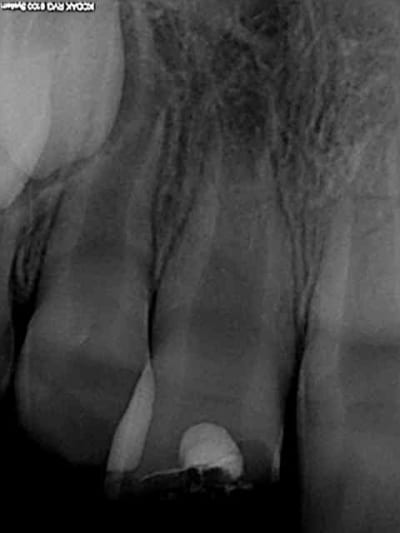

Cas concret, patient 8 ans fracture de la 11 avec effraction pulpaire. Traitement mta dans la chambre collage du morceau cassé et oh! miracle 8 mois après pont dentinaire et apexogenèse en branle. Cout 120 euros le sachet de mta. La sécu rembourse une pulpo à 16.87 euros juste de quoi mettre un eugenate et de découvrir l'apex béant avec en plus une bonne pèche 6 mois plus tard et dent nase. Les parents du patient vont témoigner sur lcp que les dépassements d'honoraires sont une honte ? Quel pays lamentable.

Bravo mais là, j'aurai mis du HN pour facturer le MTA.

Que je sache, l'apexogénèse n'est pas dans la NGAP.

HN 150 euros. 30 euros de marge, le cochon !